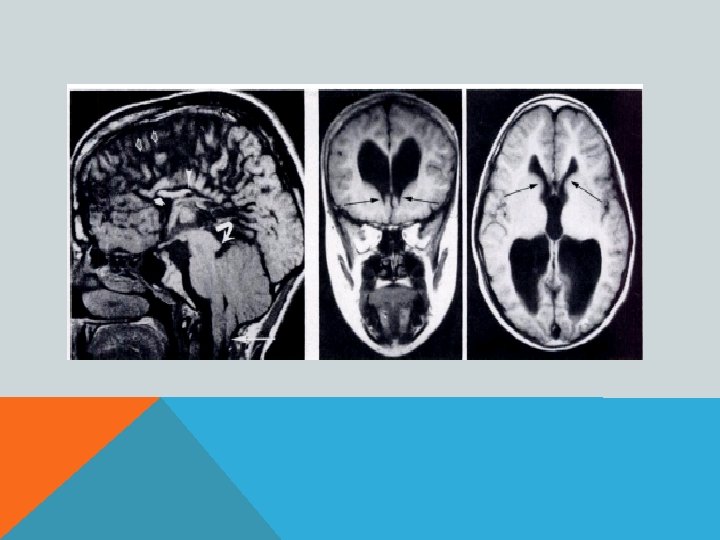

ПОРОК АРНОЛЬДА-КИАРИ 1 Увеличение миндалин мозжечка, их опущение в большое затылочное отверстие и далее, в спинномозговой канал- «нижний» вариант. Характерно образование сирингомиелической полости в шейном отделе спинного мозга. Основные клинические проявления- сирингомиелия.

ПОРОК АРНОЛЬДА-КИАРИ 1 Увеличение горки червя мозжечка и его смещение в межножковую цистерну- «верхний» вариант. Основные клинические проявления- расстройство равновесия (головокружение? )

ПОРОК АРНОЛЬДА-КИАРИ 2 Увеличение миндалин мозжечка, их опущение в большое затылочное отверстие и далее, в спинномозговой канал. «Щелевидный» 4 -й желудочек. Гипоплазия подушки моста мозга. Гипо-/аплазия мозолистого тела. Сирингомиелическая полость в шейном отделе спинного мозга. Фенестрация фалькса (серпа мозга) и т. д. В 70% сочетается со спинномозговой грыжей.